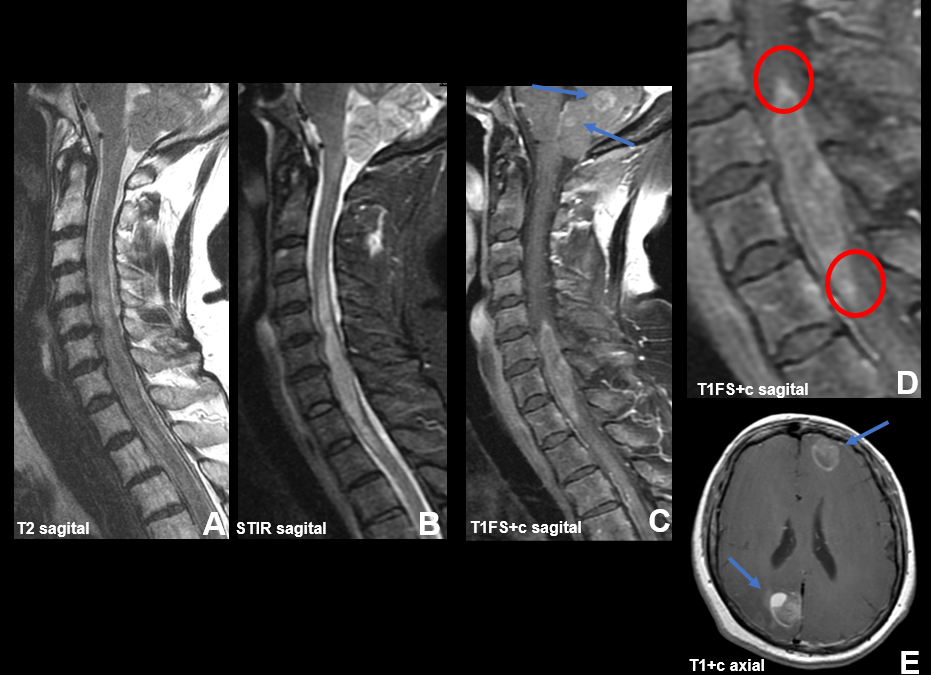

La secuencia DWI en el plano axial (A) muestra hiperintensidad de señal centrada en el cuerpo estriado izquierdo, córtex frontotemporal y caudado derecho, que se corresponde con valores bajos en el mapa ADC (B). En la secuencia FLAIR axial (C) también se observa hiperintensidad de señal en las áreas involucradas. La secuencia T1 axial post-contraste (D) no denota focos de realce patológico. En la imagen axial de PET 18-FDG (E) se aprecia hipometabolismo moderado en caudado izquierdo y córtex frontoparietal.

– Imagen: La modalidad de imagen de elección es la RM y los hallazgos radiológicos más característicos son la restricción a la difusión en núcleos caudados, putamen y córtex, de distribución bilateral y asimétrica. La hiperintensidad T2-FLAIR, aunque más sutil que los cambios de DWI, también se puede observar. La secuencia T1 postcontraste no muestra realce anormal. El PET con fluorodesoxiglucosa-18 (FDG) revela hipometabolismo en las regiones afectadas.